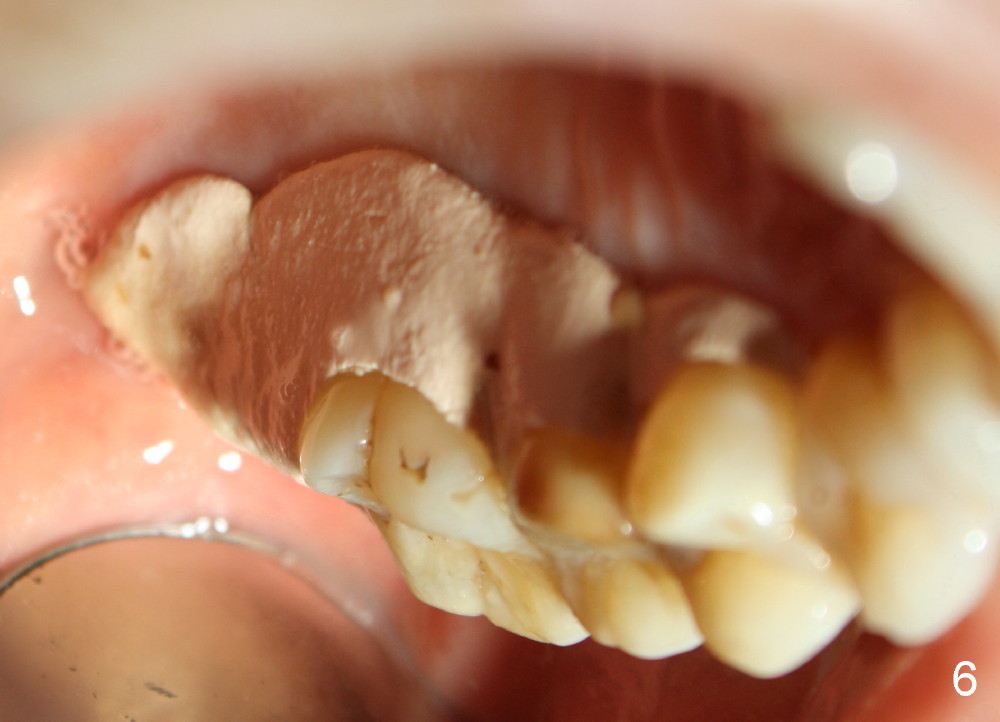

Sinus membrane integrity is checked several times intraop: there is no air leakage. There is no nasal hemorrhage or obstruction intra- or post-op. The patient returns for follow up 12 days postop; the perio dressing remains in place (Fig.6).